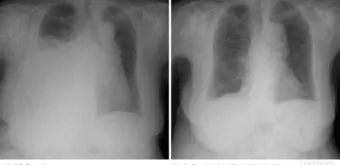

2단계, 흉부 X선 촬영입니다.

서서 찍은 단순 X선에서 보통 250mL 이상 흉수가 고이면 갈비뼈와 횡격막이 만나는 부분이 희미해지거나, 반달 모양의 음영이 보이기 시작한다고 알려져 있습니다.:contentReference[oaicite:21]{index=21}

3단계, 흉부 초음파·CT 검사입니다.

특히 초음파는 수십 mL 수준의 적은 양 흉수도 찾아내는 데 도움이 되고, 어디에 얼마나 모여 있는지를 파악해 나중에 흉강천자(물을 뽑는 시술)를 할 위치를 잡는 데 쓰입니다.:contentReference[oaicite:22]{index=22}